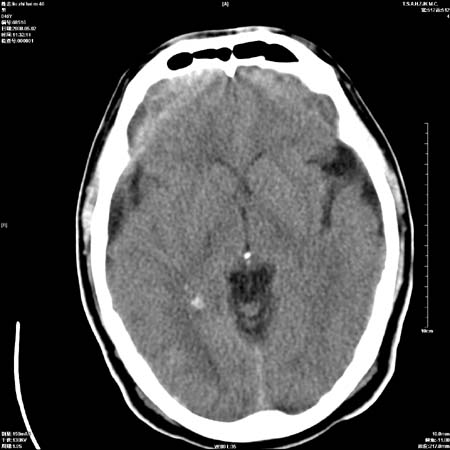

男性   46岁   头晕头痛一周    无任何外伤史    有高血压病史

亚急性硬膜下血肿

考虑双侧慢性硬膜下出血

支持双侧慢性硬膜下血肿。

应该是亚急性(3天——3周)硬膜下出血

亚急性硬膜下血肿;典型。